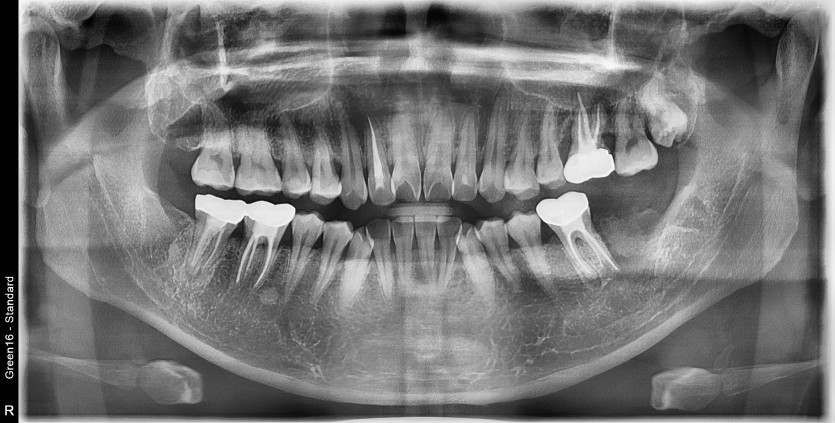

#38 사랑니 발치(#37 같이 발치)

구강 외과 전문의가 당일 발치했습니다.